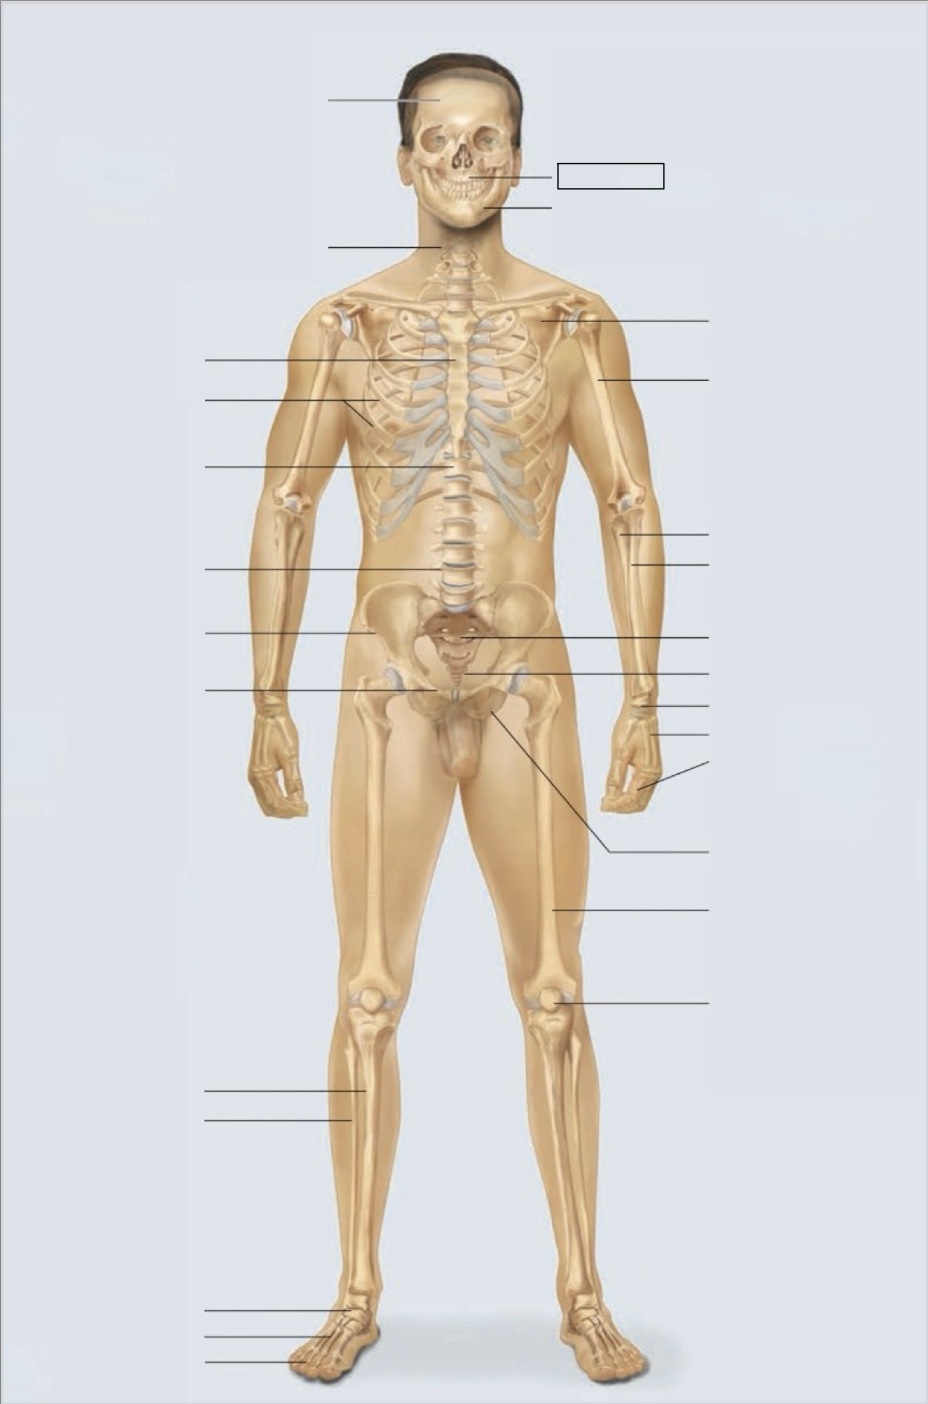

maxilla

mandible

scapula

humerus

ulna

radius

sacrum

coccyx

carpals

metacarpals

phalanges

ischium

femur

patella

phalanges

metatarsals

tarsals

fibula

tibia

pubis

ilium

lumbar vertebrae (L4)

thoracic vertebrae (T11)

ribs

sternum

cervical vertebrae

skull